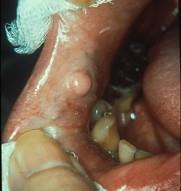

问题 组图为口内纤维瘤的外观,关于此病的描述不正确的是 ( )

选项 A.生长一般较缓慢 B.手术后不易复发 C.主要由纤维组织构成 D.有可能恶变 E.肿瘤边界清楚

答案 B